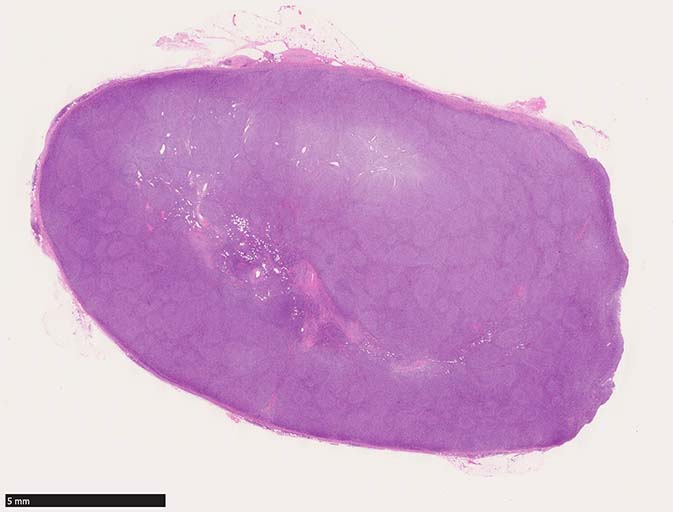

HE組織像

鼠径リンパ節病理標本(初発時リンパ節標本)

鼠径リンパ節生検組織では, びまん性に中~大型のcentroblasticまたはimmunoblastic cellsが密に増殖しCD21染色を行っても明らかな濾胞形成は認められない.

diffuse patternの増殖を示すリンパ腫病変と考える.